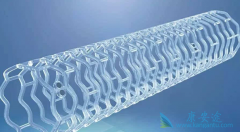

心脏支架作为现代心血管医学发展中的一个里程碑,确实在冠心病的治疗中发挥着非常重要的价值。 生物可降解支架 给冠心病介入治疗带来了新的革命。但是生物可降解支架真的能成为心血管患者的福音吗?目前心脏支架主要分为不可降解支架和完全降解支架两个 ...

生物可降解支架 安全吗?其实早在20世纪90年代初,就已经提出生物可降解支架的概念,但发展没有金属裸支架和药物洗脱支架快,最终被药物洗脱支架所替代。目前药物洗脱支架长期随访发现潜在的支架内血栓风险,最近10余年生物可降解支架科技和材料学取得 ...